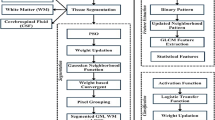

This paper is an effort to encapsulate the various developments in the domain of different unsupervised, supervised and half supervised brain anomaly detection approaches or techniques proposed by the researchers working in the domain of the Medical image segmentation and classification. As researchers are constantly working hard in the domain of image segregation, interpretation and computer vision in order to automate the task of tumour segmentation, anomaly detection, classification and other structural disorder prediction at an early stage with the aid of computer. The different medical imaging modalities are used by the doctors in order to diagnose the brain tumour and other structural brain disorders which are an integral part of diagnosis and prognosis process. When these different medical image modalities are used along with various image segmentation methods and machine learning approaches tends to perform brain structural disorder detection and classification in a semi-automated or fully automated manner with high accuracy. This paper presents all such approaches using various medical image modalities for the accurate detection and classification of brain tumour and other brain structural disorders. In this paper, all the major phases of any brain tumour or brain structural disorder detection and classification approach is covered begin with the comparison of various medical image pre-processing techniques then major segmentation approaches followed by the approaches based on machine learning. This paper also presents an evaluation and comparison among the various popular texture and shape based feature extraction methods used in combination with different machine learning classifiers on the BRATS 2013 dataset. The fusion of MRI modalities used along with the hybrid features extraction methods and ensemble model delivers the best result in terms of accuracy.